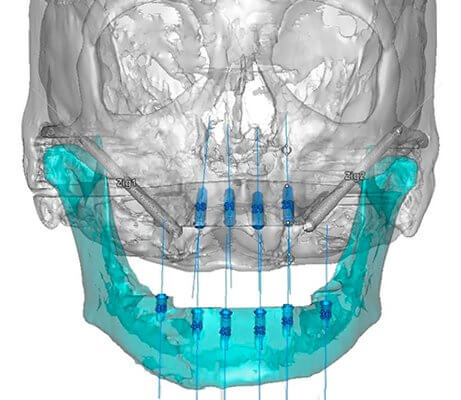

La cirugía oral guiada (COG) es una técnica innovadora que utiliza tecnología de imagen digital 3D, como la tomografía computarizada (TC) o el escáner CBCT, para planificar y realizar procedimientos quirúrgicos orales con mayor precisión y seguridad. A través de un software especializado, se crea un modelo tridimensional virtual de la boca del paciente, permitiendo al cirujano visualizar con exactitud la anatomía ósea, la posición de los dientes, los nervios y otras estructuras importantes. Este plan virtual se traduce luego en una guía quirúrgica física, normalmente hecha de plástico, que se utiliza durante la cirugía para guiar la colocación precisa de implantes dentales, extracciones complejas o cualquier otra intervención quirúrgica oral. En esencia, la COG minimiza la invasión, reduce el tiempo de cirugía y maximiza la precisión del procedimiento, resultando en una recuperación más rápida y confortable para el paciente.

La planificación preoperatoria es un paso crucial en la COG. Comienza con la obtención de un escáner CBCT o TC de alta resolución de la boca del paciente. Esta imagen 3D se importa luego a un software especializado de planificación quirúrgica, donde el cirujano analiza la anatomía ósea, la posición de los dientes, los nervios y otras estructuras importantes. Basándose en este análisis, el cirujano diseña el plan quirúrgico virtual, determinando la posición ideal para los implantes, el tamaño y el tipo de implante necesario, y la trayectoria óptima de la fresa quirúrgica. Este plan se utiliza luego para fabricar una guía quirúrgica personalizada que se utilizará durante la cirugía para guiar la colocación precisa de los implantes.

- Obtención de imágenes 3D: Se realiza un escáner CBCT o TC de alta resolución.

- Análisis de la imagen: El cirujano analiza la anatomía ósea y las estructuras circundantes.

- Diseño del plan quirúrgico virtual: Se determina la posición, tamaño y trayectoria de los implantes.

Materiales y Tecnología Utilizada en Cirugía Oral Guiada

La COG se basa en el uso de tecnología avanzada de imagen y software especializado. El escáner CBCT o TC proporciona imágenes tridimensionales de alta resolución de la boca del paciente. Existen diferentes softwares de planificación quirúrgica, cada uno con sus propias características y funcionalidades, que permiten al cirujano diseñar el plan quirúrgico virtual y generar la guía quirúrgica. La guía quirúrgica misma, normalmente fabricada con plástico de alta precisión, actúa como una plantilla que guía la fresa quirúrgica durante la cirugía, asegurando la precisión y la seguridad del procedimiento. Además, se utilizan instrumentos quirúrgicos específicos diseñados para trabajar con la guía.

- Escáner CBCT o TC: Para obtener imágenes 3D de alta resolución.

- Software de planificación: Para diseñar el plan quirúrgico virtual y generar la guía quirúrgica.

- Guía quirúrgica: Una plantilla de plástico que guía la fresa quirúrgica durante la cirugía.

Una guía quirúrgica dental es un dispositivo de precisión, generalmente fabricado con materiales como el titanio o la resina, que se utiliza para planificar y realizar procedimientos quirúrgicos orales con mayor precisión y seguridad. Se diseña individualmente para cada paciente basándose en imágenes de diagnóstico por imagen, como CBCT (tomografía computarizada de haz cónico), y sirve como una plantilla que guía al cirujano durante la colocación de implantes dentales, injertos óseos, o cualquier otro procedimiento quirúrgico complejo en la boca. Su objetivo principal es minimizar la invasión quirúrgica, reducir el tiempo de operación, mejorar la precisión de la colocación de los implantes o injertos y, en consecuencia, maximizar las posibilidades de éxito del tratamiento. Se utilizan para asegurar la posición, la profundidad y el ángulo correctos de los implantes, minimizando el riesgo de daño a estructuras anatómicas importantes como nervios o senos maxilares.

Proceso de Fabricación de una Guía Quirúrgica Dental

- Obtención de imágenes CBCT: Se realiza un escáner CBCT del paciente para obtener imágenes tridimensionales de la anatomía oral.

- Planificación virtual: El software de planificación CAD/CAM permite al cirujano diseñar la posición ideal de los implantes y la guía quirúrgica.

- Fabricación de la guía: La guía se fabrica a través de técnicas de fresado o impresión 3D, utilizando materiales biocompatibles.